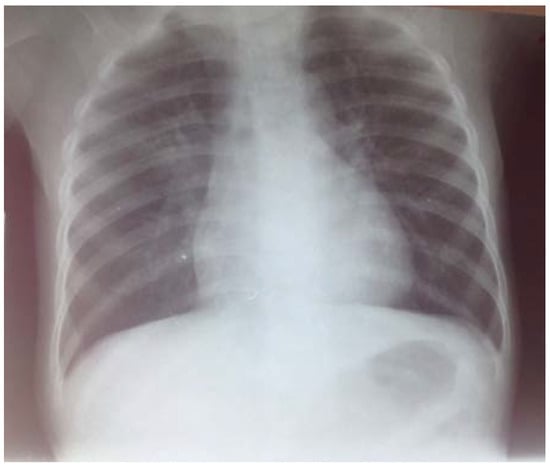

The patient was started on treatment protocol for malnutrition, community acquired pneumonia and cutaneous staphylococcal infection including milk F-75 (formula 75, a supplementary starter milk for feeding malnourished children, contains 75 kilocalories per 100 milliliters) 100 mL every 3 hours, cefotaxime 450 mg every 8 hours, gentamicin 20 mg once per day and cloxacillin 400 mg every 8 hours. However, infection was still present after 7 days of treatment. As the dyspnea worsened and the Keith Edward score for tuberculosis was 9 (the length of illness: more than four weeks, the nutritional status: weight for age under 60%, the malnutrition status had not improved after four weeks of treatment and the changes in temperament: anorexia), the patient began a tuberculosis treatment protocol with RHZ 1 tablet per day before breakfast (rifampicin 60 mg, isoniazid 30 mg, pyrazinamide 150 mg) and ethambutol 60 mg 1 tablet per day before breakfast. We had to discontinue cefotaxime and gentamicin after 8 days of treatment while maintaining cloxacillin for skin infection, and stopping it after 21 days. Ceftriaxone 520 mg daily was added to his treatment from the 30th day of hospitalization for a duration of 8 days. After 38 days of tuberculosis treatment, no improvement was observed while the dyspnea worsened. A new chest radiography showed a pleural effusion (Figure 2).

Figure 2.

Chest X-ray after 45 days of admission. The reticular opacity fills both pulmonary fields and there are signs of pleural effusion.